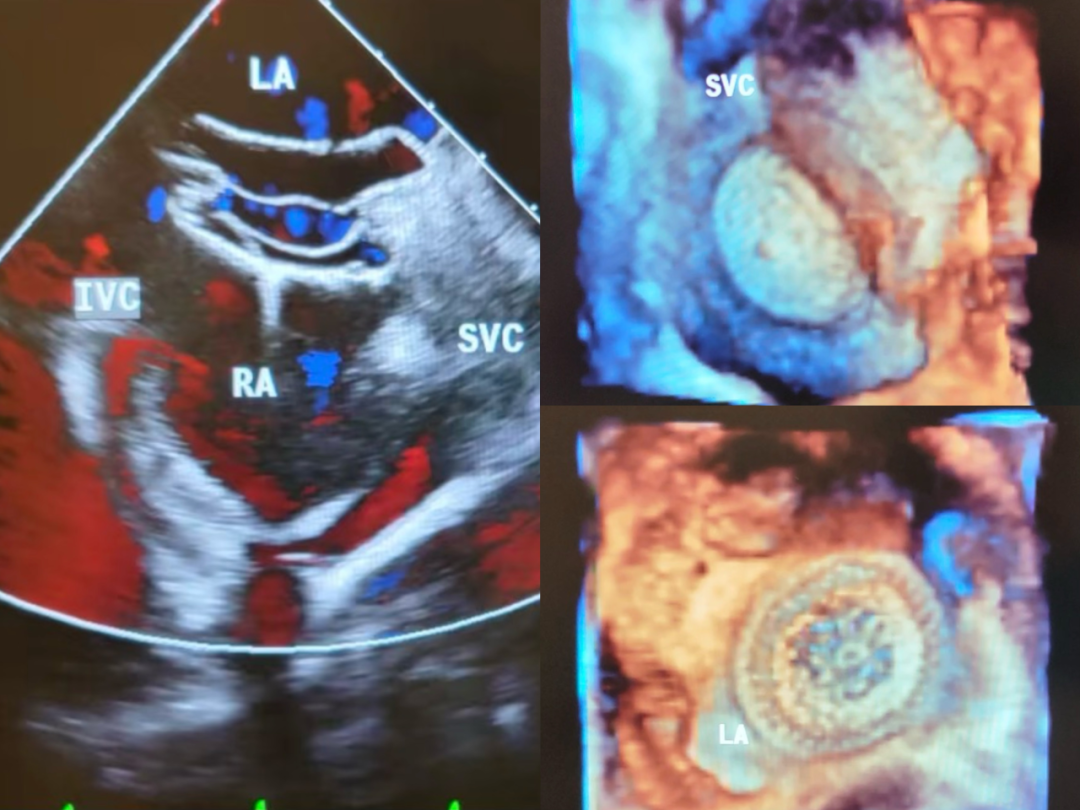

经食道超声心动图(TEE):为心脏手术及结构性心脏病介入治疗提供关键影像支持。

房间隔缺损封堵术中经食管超声心动图